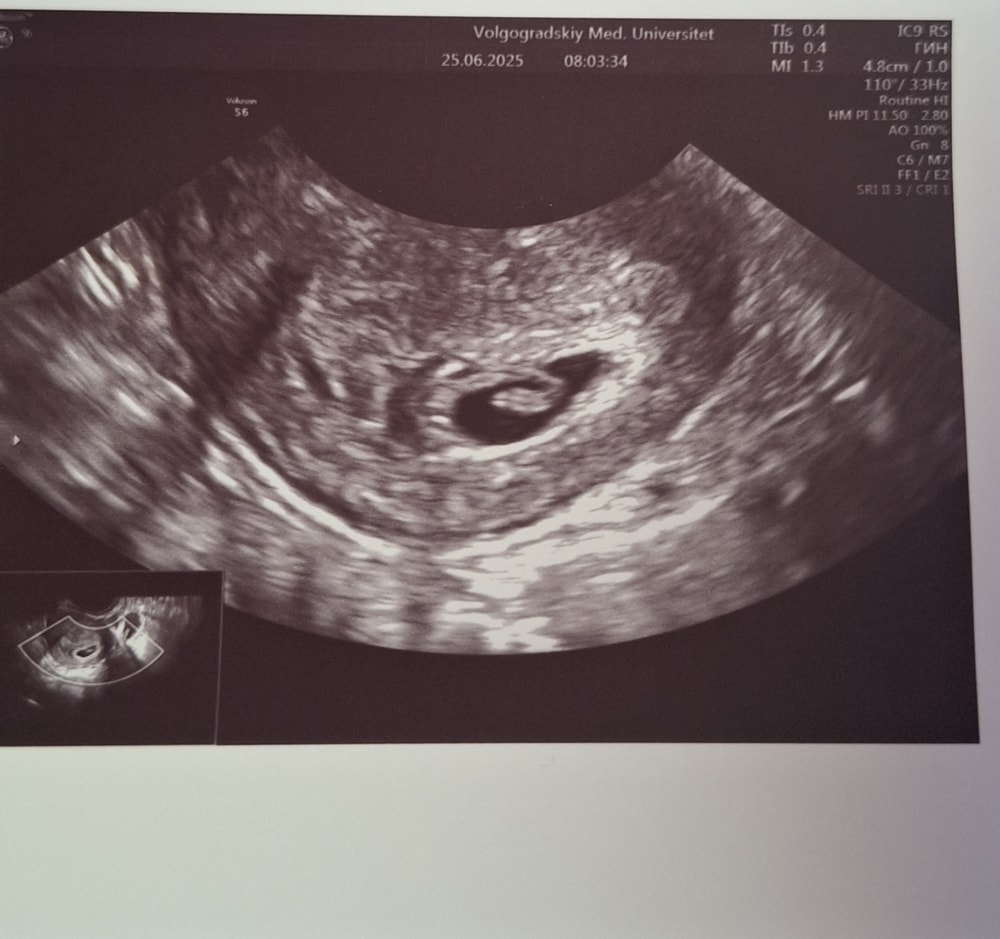

35 дпп и 2 узи

21 дпп узи Разный срок по УЗИ и календарю